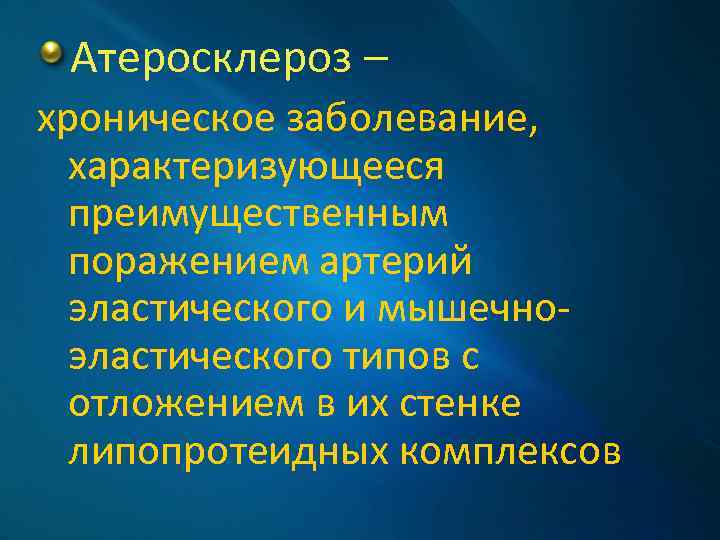

Атеросклероз – хроническое заболевание, характеризующееся преимущественным поражением артерий эластического и мышечноэластического типов с отложением в их стенке липопротеидных комплексов